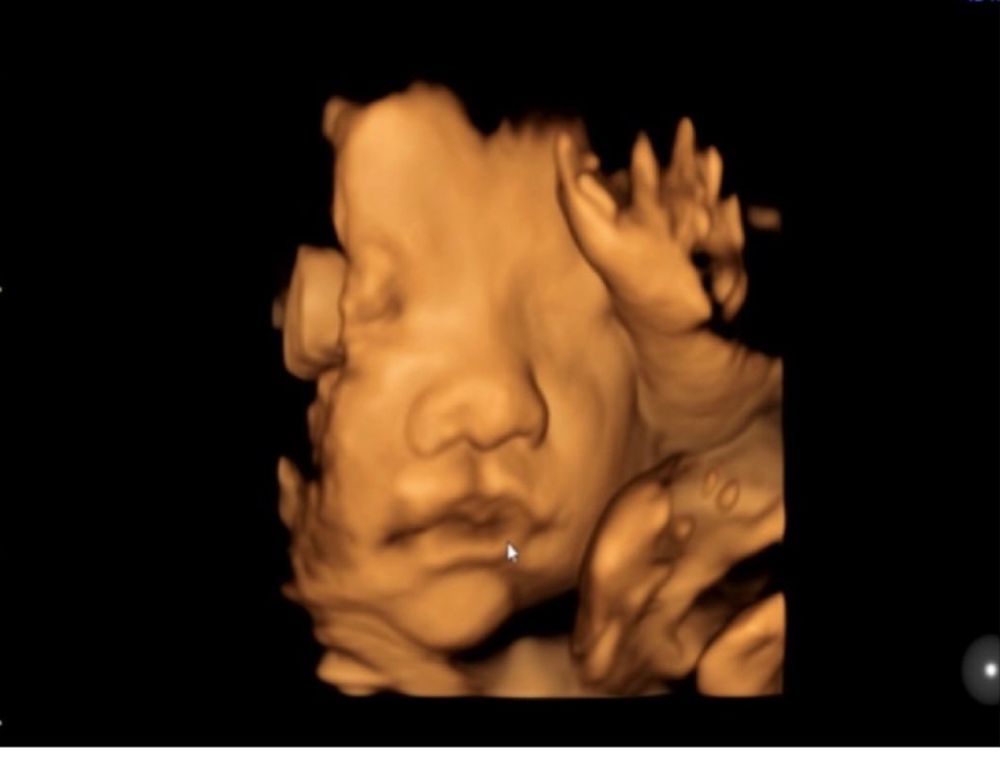

По личику пошла в папу -японца. У старших детей более европейская внешность.